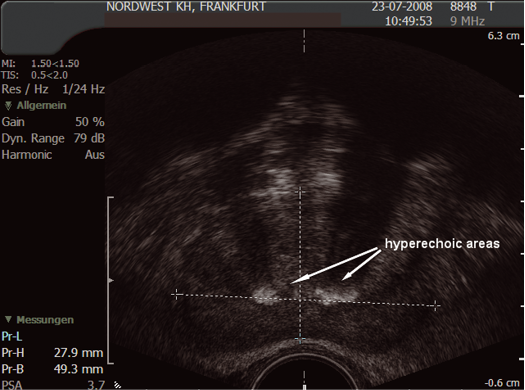

The sonographic appearance of the prostate is not specific but there are three ultrasonic findings that may be described as isoechoic (same echogenicity as surrounding tissue), hyperechoic (brighter) or hypoechoic (darker). (Figs. 10 and 11)

Fig. 10. Hyperechoic areas

(Courtesy: S. Hieronymi)

Ultrasonic findings:

- isoechoic area could be normal tissue or tumour

- hypoechoic area could be cyst, abscess or tumour

- hyperechoic area could be calcification or tumour

Although these findings are interesting, they should not have any impact on the biopsy procedure or cause additional complications.